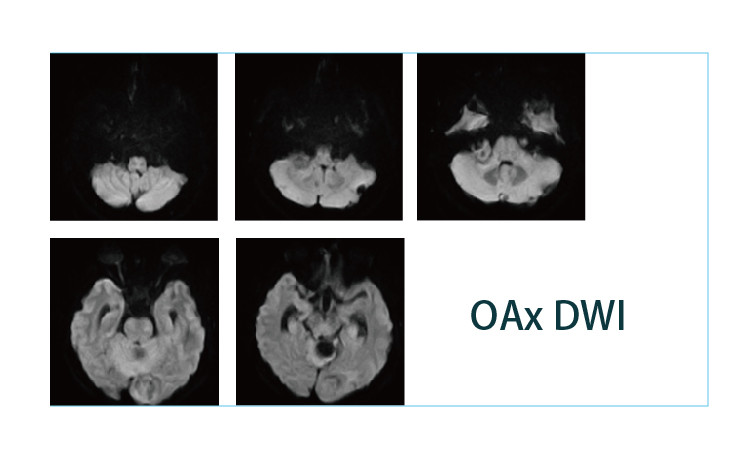

【朗润影像档案】20190419磁共振影像病例结果讨论

【朗润影像档案】磁共振影像病例分享(编号20190419)